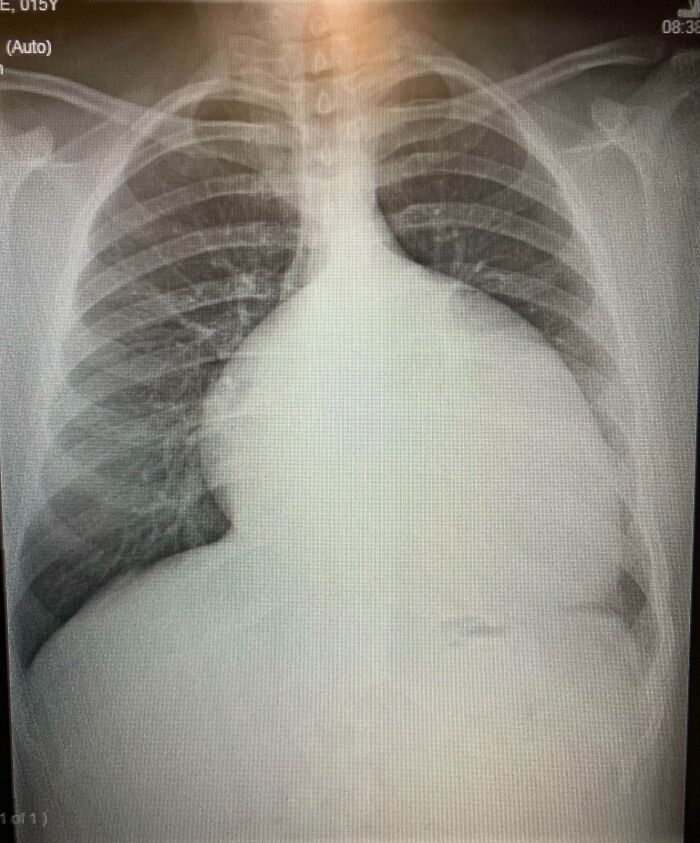

#18 My Enlarged Heart At Age 15 (2012) Before I Had Surgeries